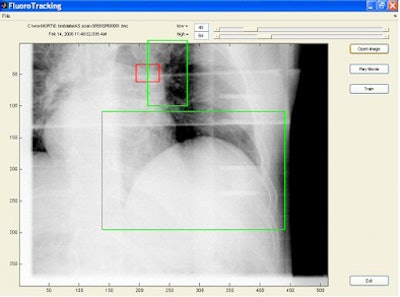

| Tumor is in red rectangular region and is invisible in the image. Two green regions are selected as surrogate windows, from which motion information is extracted using machine-learning techniques to derive the position of the invisible tumor. Image provided by Steve Jiang, Ph.D., University of California, San Diego. |